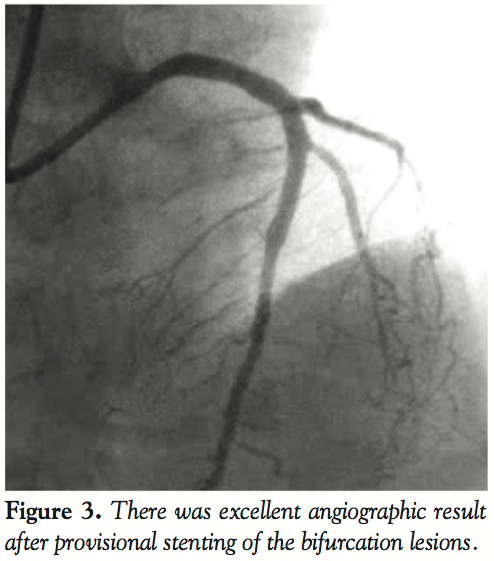

cook Flexor sheath (Cook) as inside dilator in a 7 Fr EBU 3.5 guiding catheter (Medtronic Medical) (Figure 1). The LAD/diagonal bifurcation lesions were treated with a 3.5 mm x 15 mm Promus stent (Boston Scientific) and kissing balloon inflations of LAD/diagonal lesions (Figure 2). The final angiogram showed excellent result (Figure 3). The patient did clinically well and was able the leave the hospital the following day. Ulnar artery was patent by palpation and plethysmography at 1-, 7-, and 30-day follow-up.